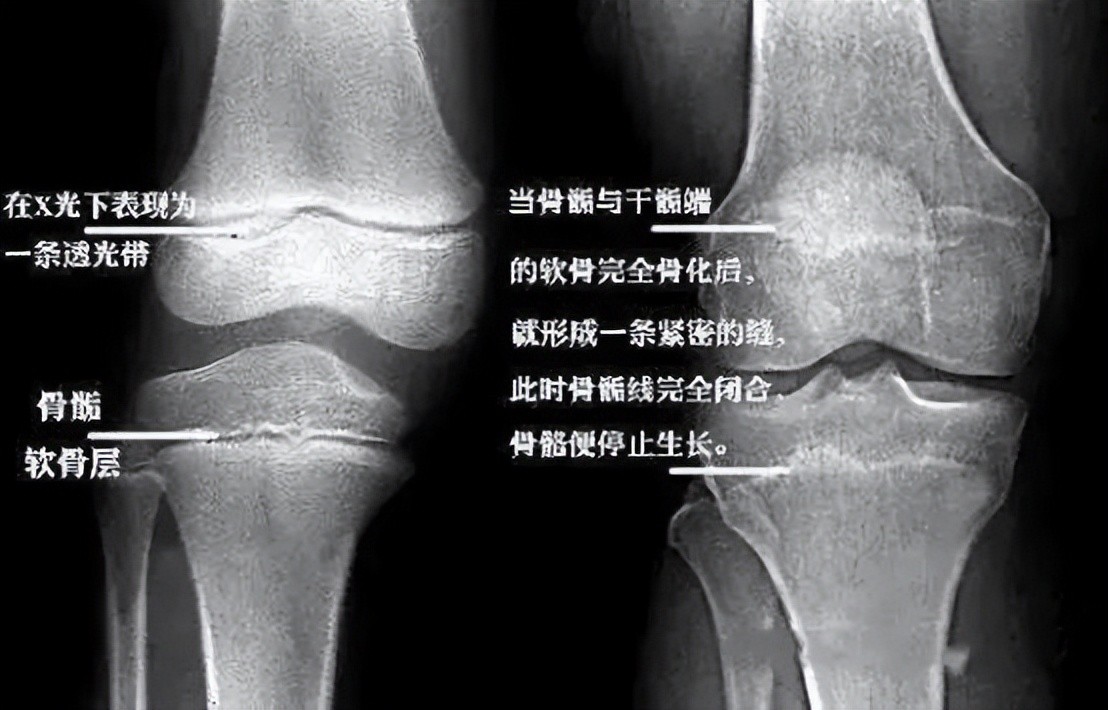

“你这骨骺线已经完全闭合,没有长高的可能了。”

随后医生解释到,骨骼生长是依靠细胞的增值分化,而这些细胞就在长骨干端上,如果骨骺线闭合,就意味着细胞已经无法增值分化,也就无法再长高了。